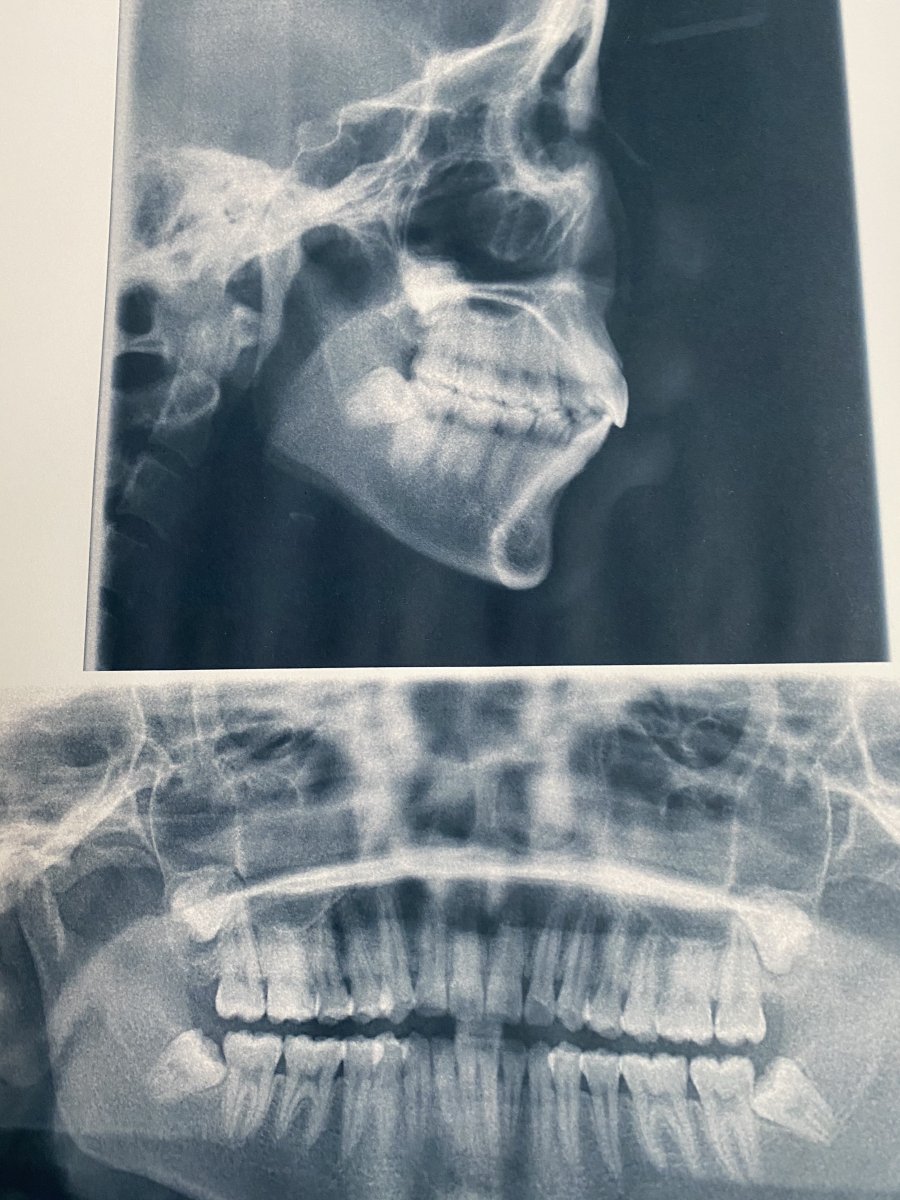

The starting point of this project is me going to see the dentist. I found out the mouth could be a interesting idea to research as a shared space. Here's some visual primary research.

My mouth scanning

kept receipts of seeing the dentist